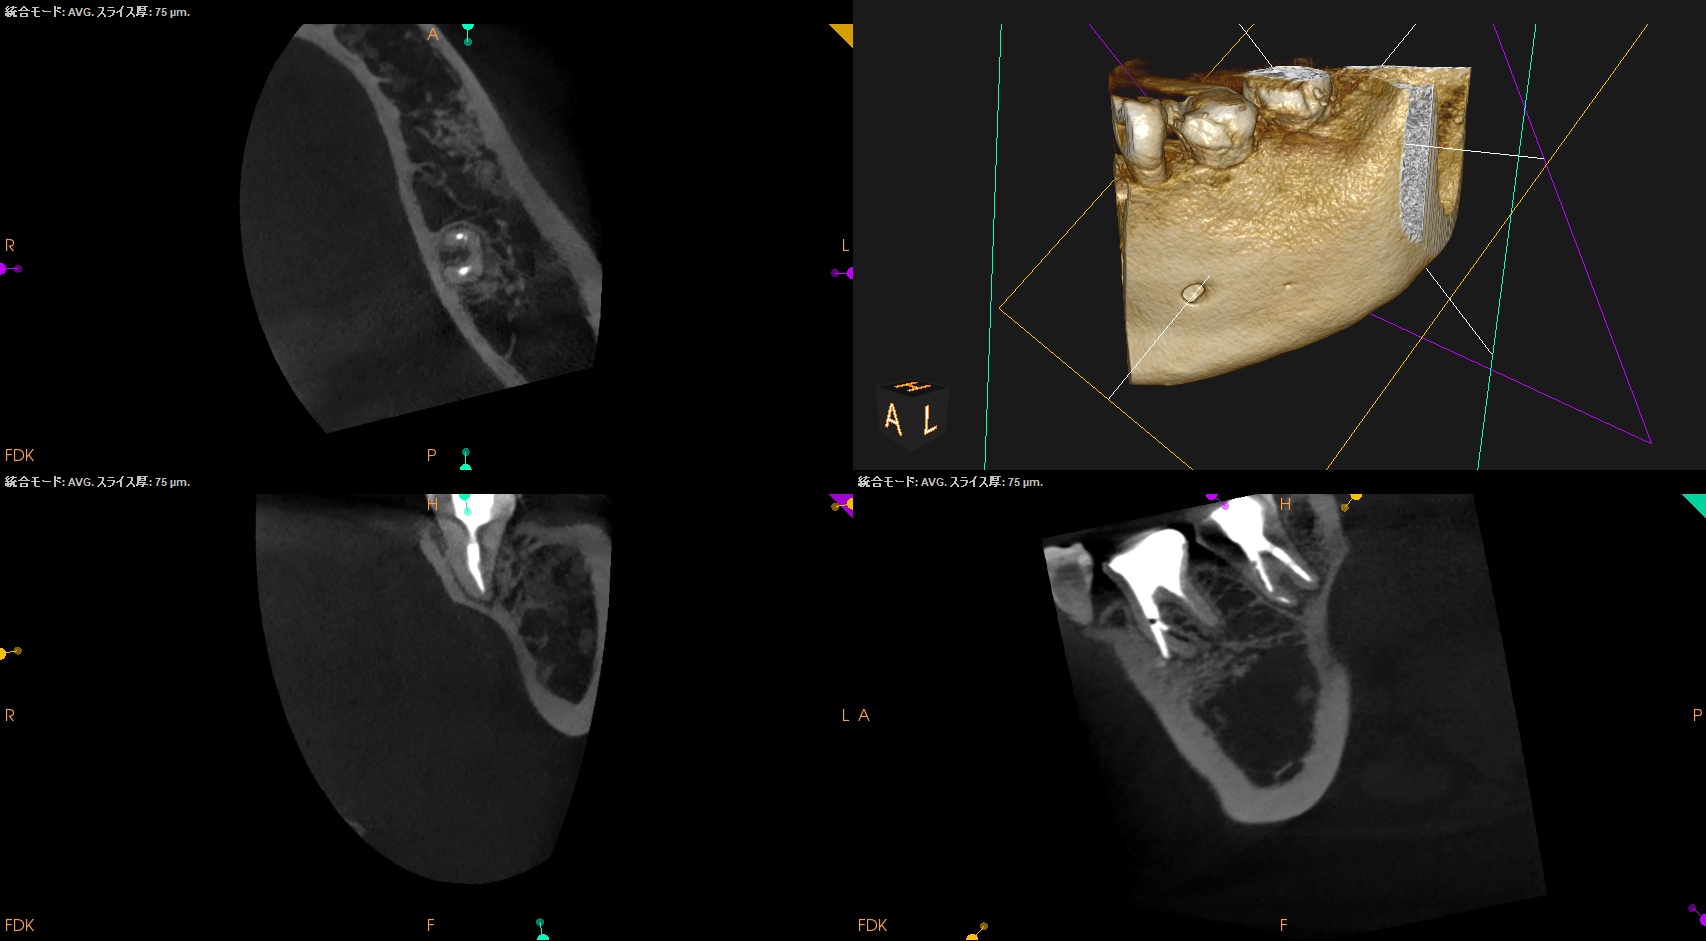

CBCTも撮影した。

#18 MB

#18 D

が、PAやパノラマで見られたような初見はCBCTでは得られなかった。

むしろ、近心根の根尖部に病変があるように見える。

ともあれ、#18は樋状根であるということがわかる。